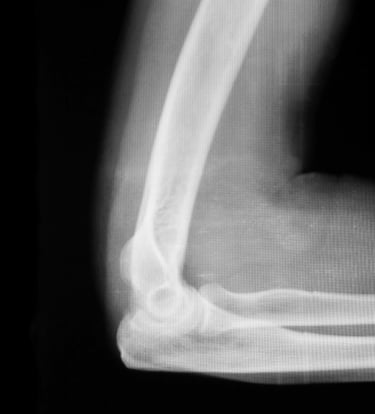

Gydytojas Markas Fiodorovas - ortopedas traumatologas, sporto traumų specialistas, sukaupęs 20 metų patirtį tausojančioje artroskopinėje chirurgijoje. Daugiau nei 650 artroskopinių kelio, peties ir kitų sąnarių operacijų per metus atliekantis chirurgas, taip pat aktyviai įsitraukęs į mokslinę veiklą. Gydytojas yra nuolatinis tarptautinių konferencijų lektorius bei tarptautinis artroskopinės chirurgijos instruktorius.

Gydytojas Markas Fiodorovas - ne tik vienas daugiausiai operuojančių ortopedų - traumatologų Lietuvoje, bet ir aktyvus mokslinės bendruomenės narys, lektorius bei instruktorius. LASTA ir ESKKA asociacijų narys, nuo 2010 metų nuolat skaito pranešimus tarptautinėse konferencijose. Tarptautinis artroskopinės chirurgijos kursų instruktorius nuo 2012m. moko artroskopijos chirurgus visame pasaulyje.